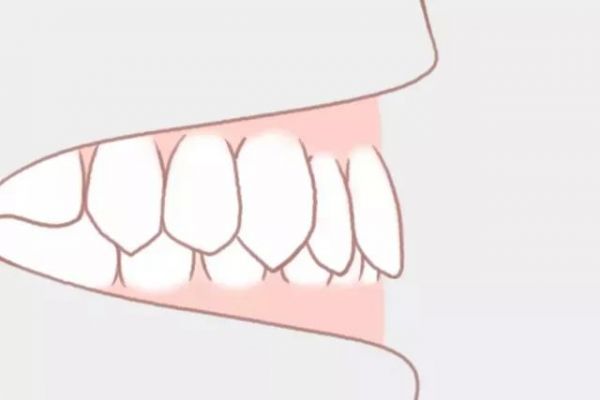

深覆颌

上牙包住下牙的范围过大,情况严重者甚至可以咬到下牙牙龈。